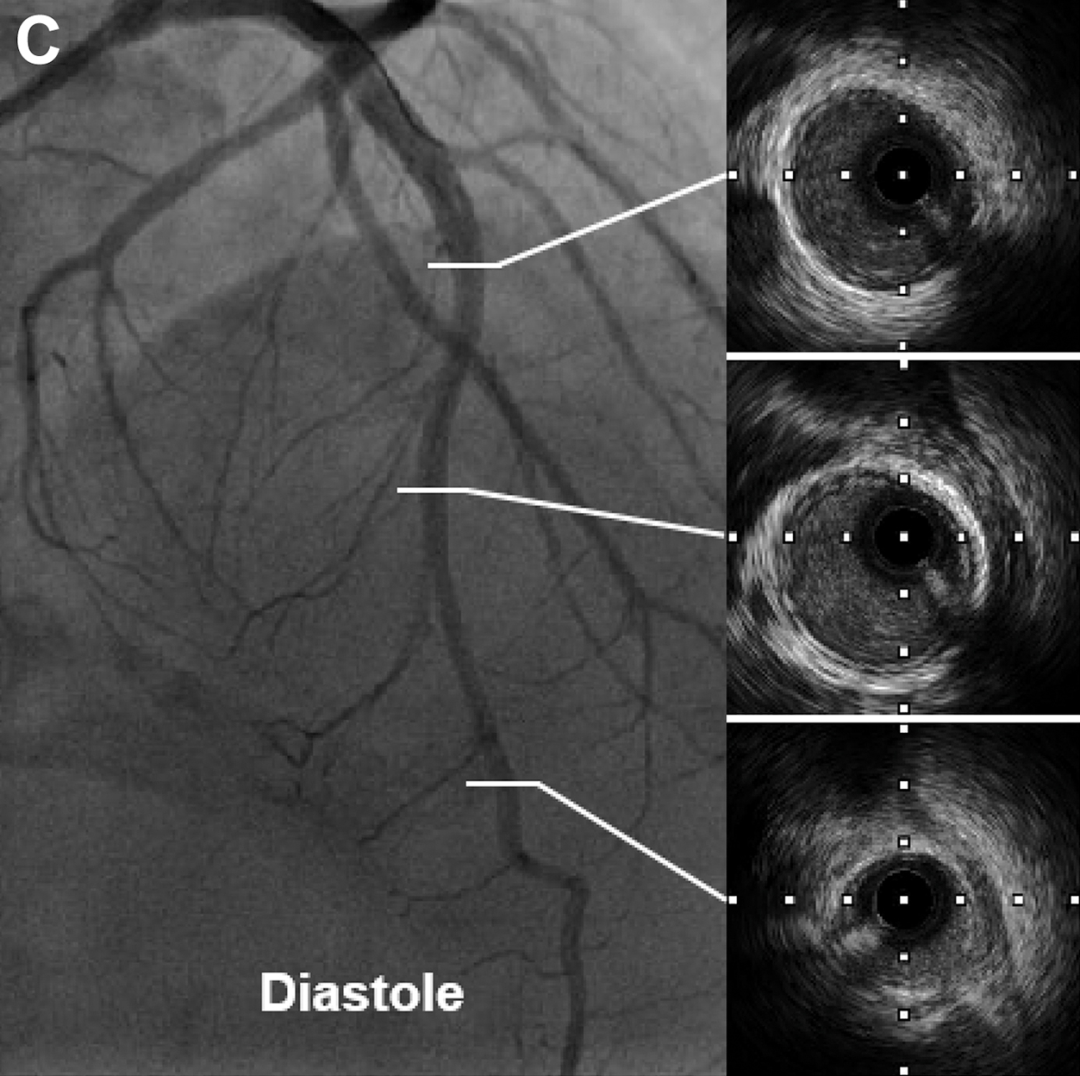

冠状动脉造影显示前降支存在孤立性心肌桥,伴有典型的 "挤奶现象";冠脉内注射硝酸甘油后,该效应加重(图C 和D)。其他心外膜动脉未发现狭窄。进一步的IVUS显示在出现"挤奶现象"的节段存在 "半月现象",这是心肌桥的典型特征。通过 β 受体阻滞剂(琥珀酸美托洛尔 23.75mg,每日一次)和抗焦虑药物(盐酸舍曲林片 50mg,每日一次)治疗,患者症状得到缓解。

(图C和D)舒张期和收缩期前降支的典型冠脉造影及对应IVUS图像。